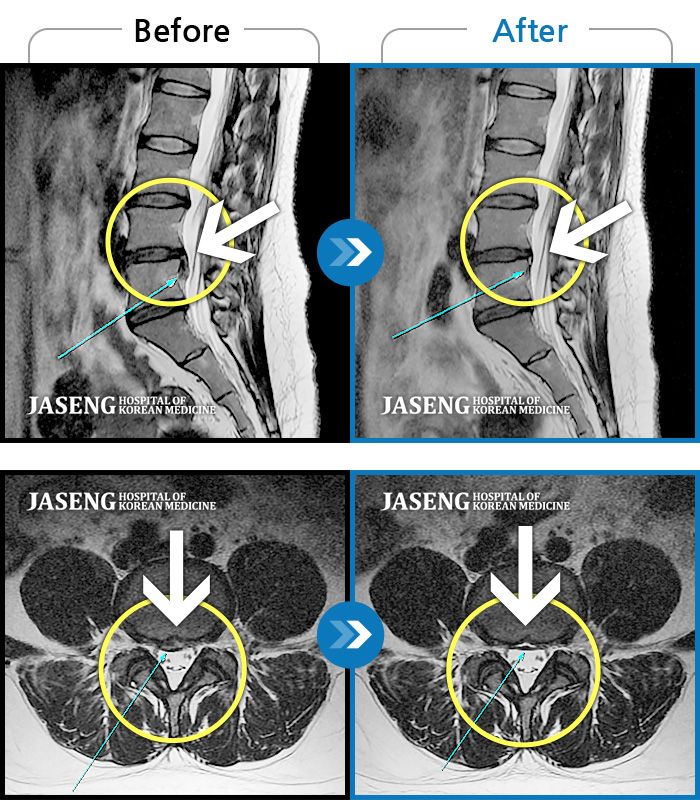

허리디스크

분당 · 진은석 원장

허리통증과 좌측 엉덩이에서 다리까지 방사통, 야간통

촬영시기

2018.12.27 ~ 2019.07.06

2019.07.26

조회수 12,731